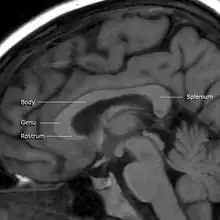

![]() Corpus callosum from above, front part at the top of the image. | |

A number of separate nerve tracts, classed as subregions of the corpus callosum, connect different parts of the hemispheres. The main ones are known as the genu, the rostrum, the trunk or body, and the splenium.[4]

The corpus callosum has four main parts – individual nerve tracts that connect different parts of the hemispheres. These are the rostrum, the genu, the trunk or body, and the splenium.[4] A narrowed part between the trunk and the splenium is known as the isthmus. Fibres from the trunk and the splenium known together as the tapetum form the roof of each lateral ventricle.[6]

The front part of the corpus callosum, towards the frontal lobes, is called the genu ("knee"). The genu curves downward and backward in front of the septum pellucidum, diminishing greatly in thickness. The lower, much thinner part is the rostrum and is connected below with the lamina terminalis, which stretches from the interventricular foramina to the recess at the base of the optic stalk. The rostrum is named for its resemblance to a bird's beak.

The end part of the corpus callosum, towards the cerebellum, is called the splenium. This is the thickest part, and overlaps the tela choroidea of the third ventricle and the midbrain, and ends in a thick, convex, free border. Splenium translates as "bandage" in Greek.

The trunk of the corpus callosum lies between the splenium and the genu.